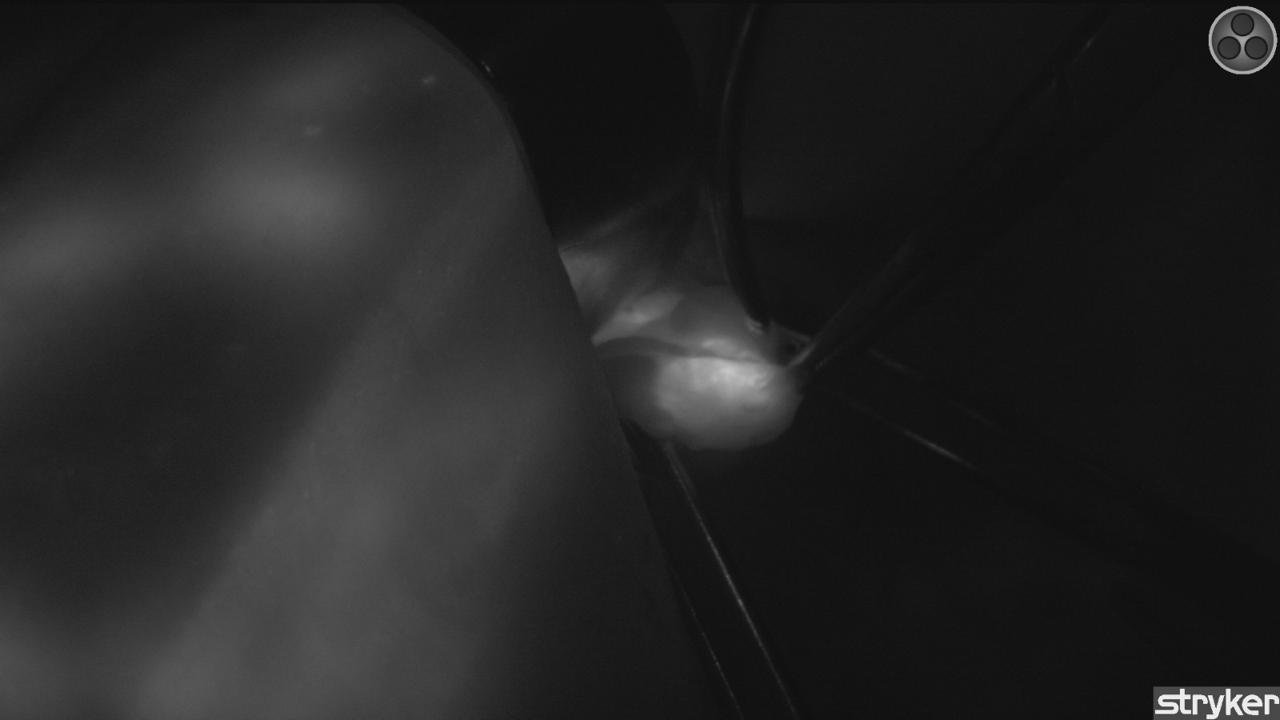

Equipo para verde de indocianina de cámara abierta

Tecnología para realizar cirugías guiadas por fluorescencia, permitiendo evaluar la perfusión de los tejidos. La alta resolución permite tener